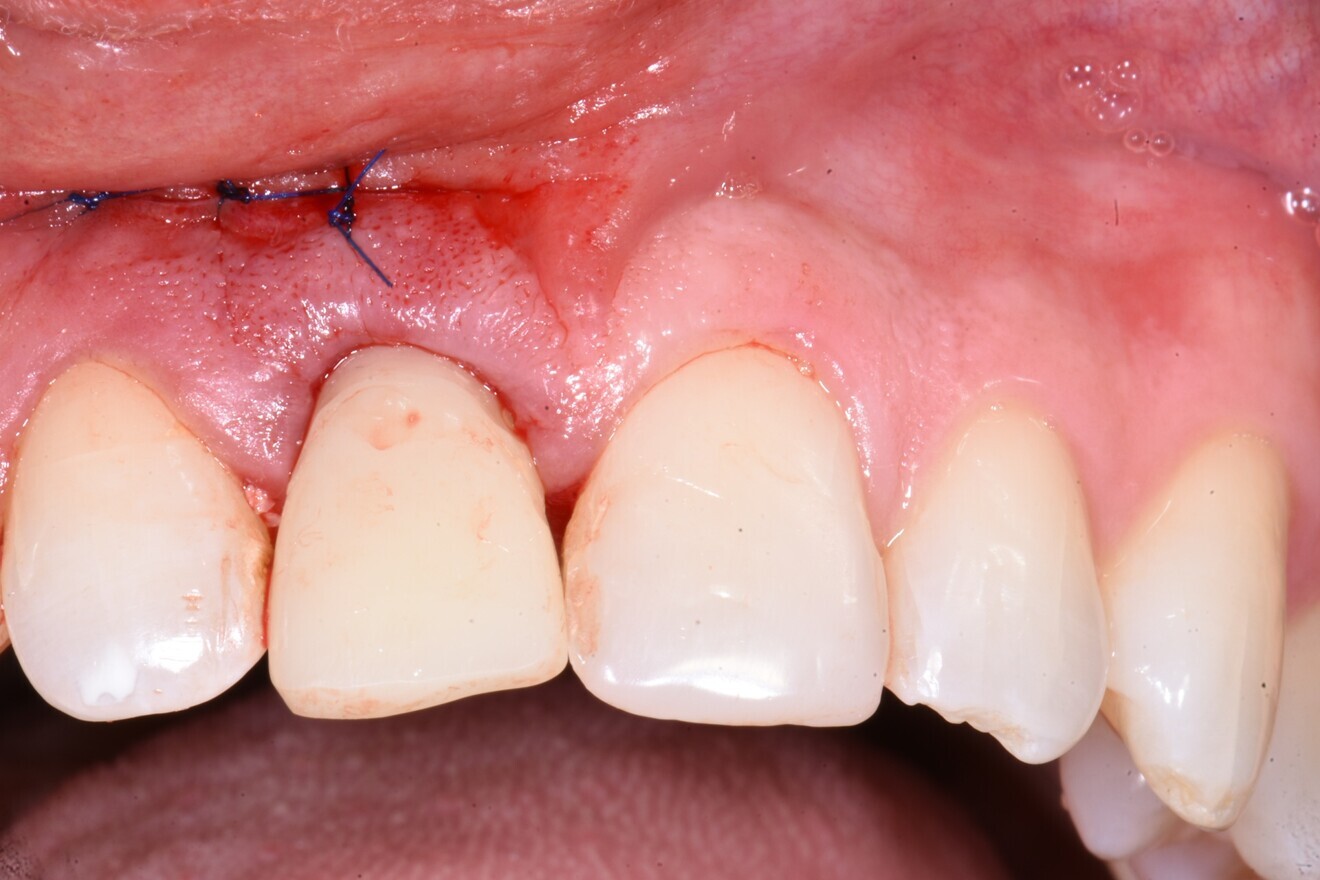

The infrabony defect was grafted with the bovine bone mineral and covered in a resorbable collagen membrane (OSSIX Plus, Dentsply Sirona) before the wound was closed and the immediate provisional restoration fabricated, which was under-contoured on purpose to allow for soft-tissue volume to increase around the neck of the crown and to bring the zenith coronally in order for it to be level with that of the adjacent central incisor (Figs. 9–11). RFA was then utilised to monitor changes in stability, increasing to 64/69 ISQ after six weeks and an impressive 79/82 ISQ after just over four months of healing. These values indicated progressive bone remodelling, graft consolidation and osseointegration and thus that the site was ready for definitive restoration.

Fig. 11: Under-contoured provisional restoration placed immediately and out of occlusal contact to allow soft-tissue fill.